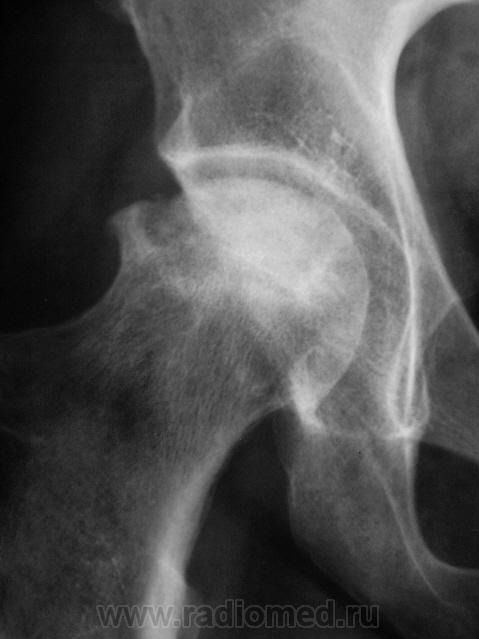

Асептический некроз головки правой бедренной кости, в стадии импрессионного перелома.

Согласен с наличием асептического некроза.

Асептический некроз. Не Пертеса, т.к. пациент явно старше 14 лет. У нас таких оперируют - эндопротез.

Да уж, господа, оставьте компанию Легг-Кальве-Пертеса в покое: этот Асептический некроз явно без них возник. Согласен с Иринкой в стадии.